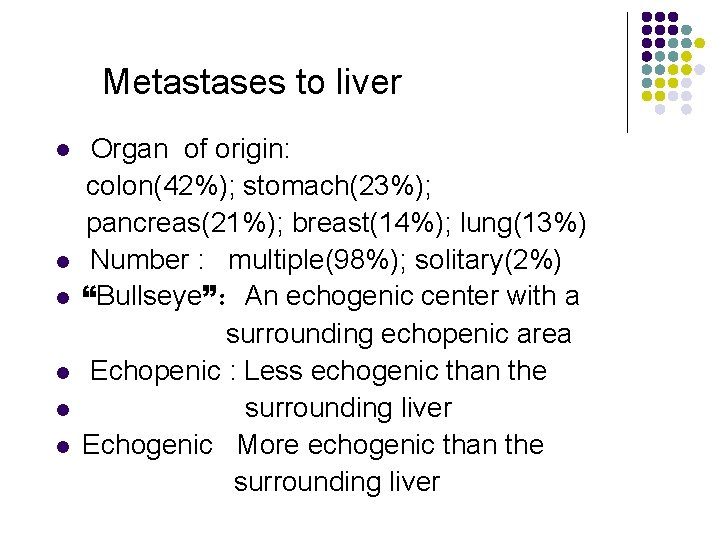

Metastases to liver l l l Organ of origin: colon(42%); stomach(23%); pancreas(21%); breast(14%); lung(13%) Number : multiple(98%); solitary(2%) “Bullseye”:An echogenic center with a surrounding echopenic area Echopenic : Less echogenic than the surrounding liver Echogenic More echogenic than the surrounding liver